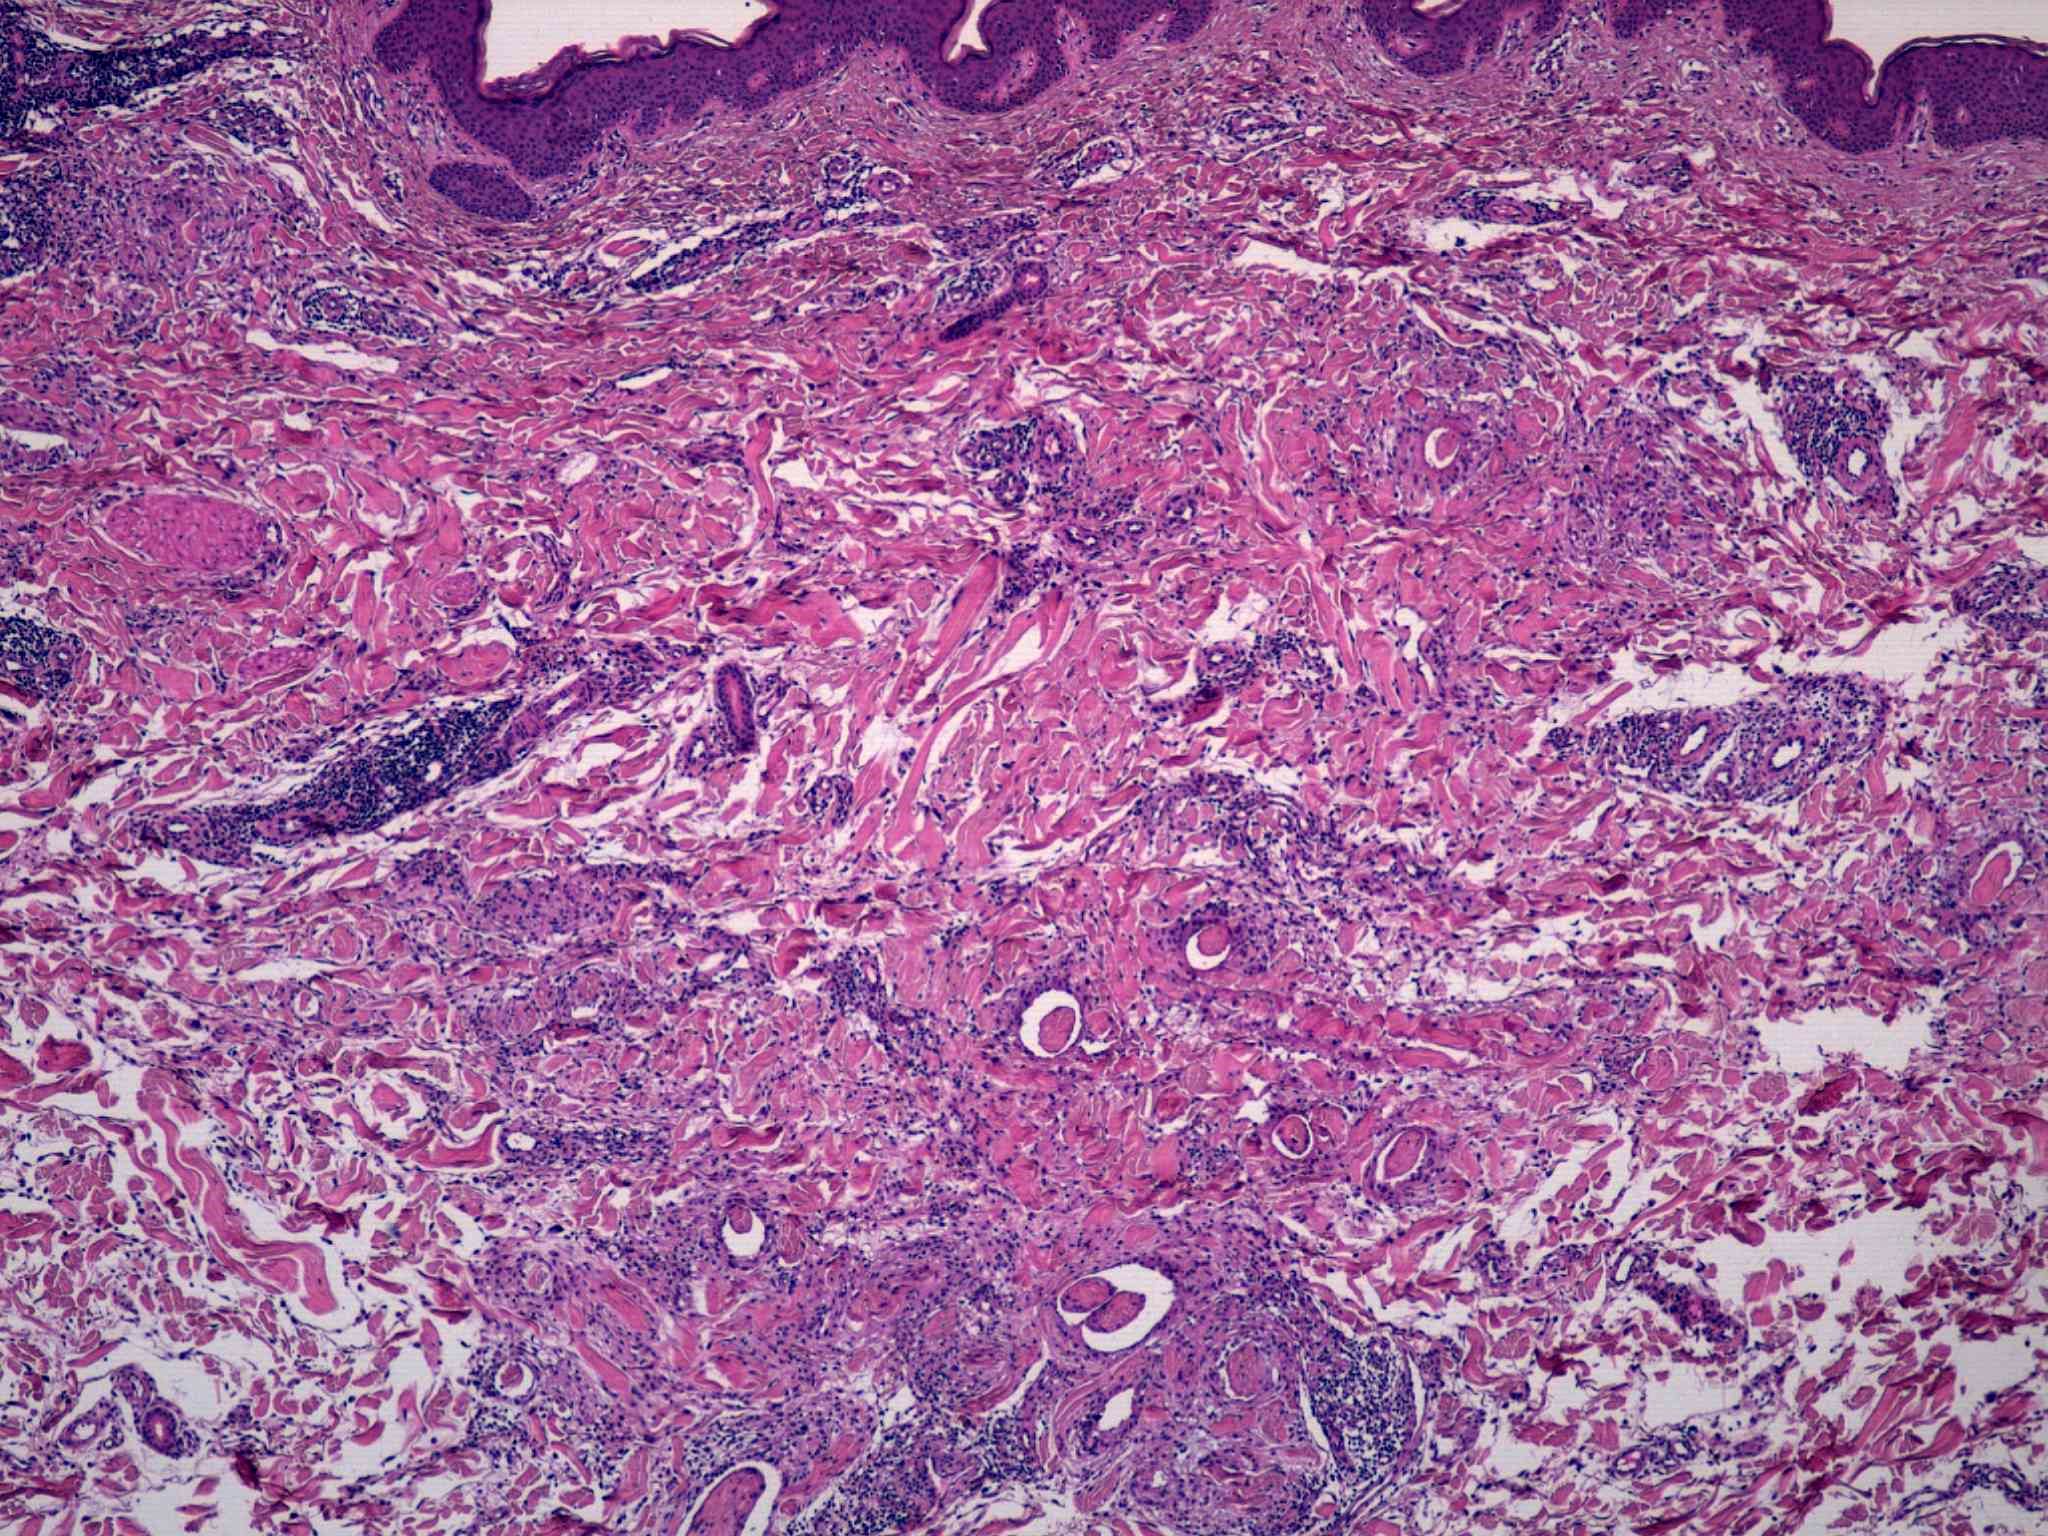

42 -- image_2011y10m04d_16h11m12s.jpg